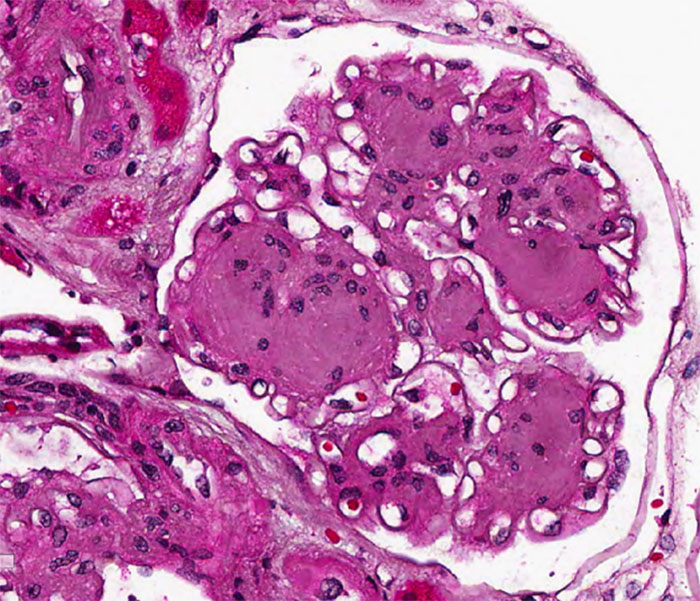

Histopathology of Diabetic Nephropathy

Classic Histologic Features (RPS Classification)

Glomerular Lesions:

1. GBM thickening (earliest lesion)

2. Diffuse mesangial expansion

3. Nodular sclerosis (Kimmelstiel–Wilson nodules)

4. Mesangiolysis

5. Capillary microaneurysms

6. Global glomerulosclerosis in advanced disease

Patchy vs Diffuse Nature

A key diagnostic nuance: diabetic lesions may be patchy and heterogeneous, especially early in T2DM. Nodular lesions may involve only some glomeruli, while adjacent glomeruli may show only mild mesangial expansion. Hence biopsy sampling error can underestimate severity.

Emerging pathology studies using deep-learning morphometry show subtle early glomerular tuft contraction and peripheral capillary alterations even before overt nodular sclerosis develops.